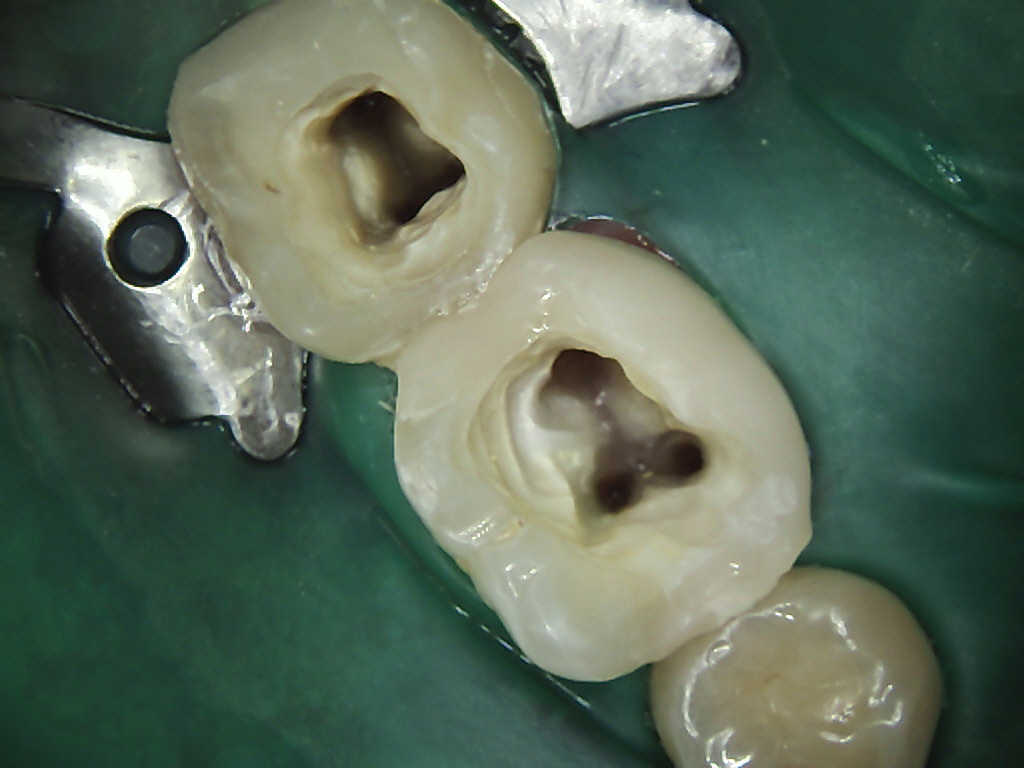

Wurzelbehandlung (Endodontie)

Ist der Defekt so tief, dass der Zahnnerv geschädigt wurde, so muss eine Wurzelbehandlung durchgeführt werden. Diese beinhaltet das saubere Entfernen

der Pulpa (Zahnnerv), die Desinfektion des Nervenkanals und eine bakteriendichte Füllung des Zahnes, um eine spätere Bakterienbesiedlung, welche zum Zahnverlust führen kann, zu verhindern.